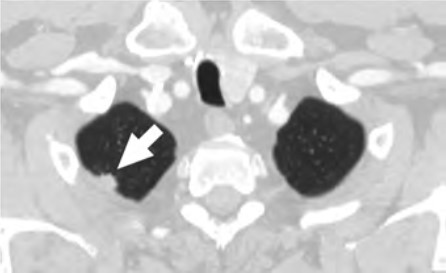

At the individual level, barriers to participation include conflicting personal and health schedules, such as medical appointment times that conflict with working hours, dependent care schedules, understanding the importance of adherence to annual LCS and recommended follow-up (Fig. 4) for the detection of early LC, anxiety and stigma about LC diagnosis, concerns about radiation exposure, and access to primary care services to get LCS referrals [4, 9, 10, 26].